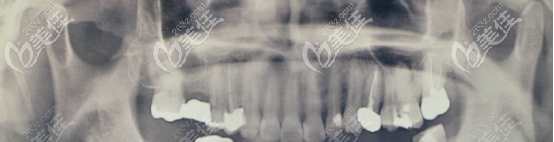

我當時做根管治療的時候根充不到位,從而炎癥再次復發(fā),導致根尖炎,沒過多久牙齦上長了一個小膿包。

(術前的口腔片)